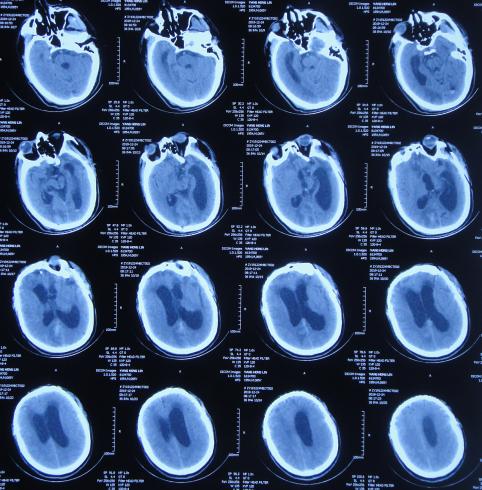

2019年10月20日患者骑电动车在马路上行驶时被大货车撞倒,当时意识清楚,只感到有些头晕,未在意就自行回家,但回家后约3-4小时出现头晕加重,并伴有恶心呕吐的症状,家人急送到当地的河北省邯郸市某医院,查头颅CT示脑出血( 图-1 );既往病史2015年曾因头部外伤致硬膜下血肿,进行了钻孔引流术。

图-1: 2019年10月20日头颅CT